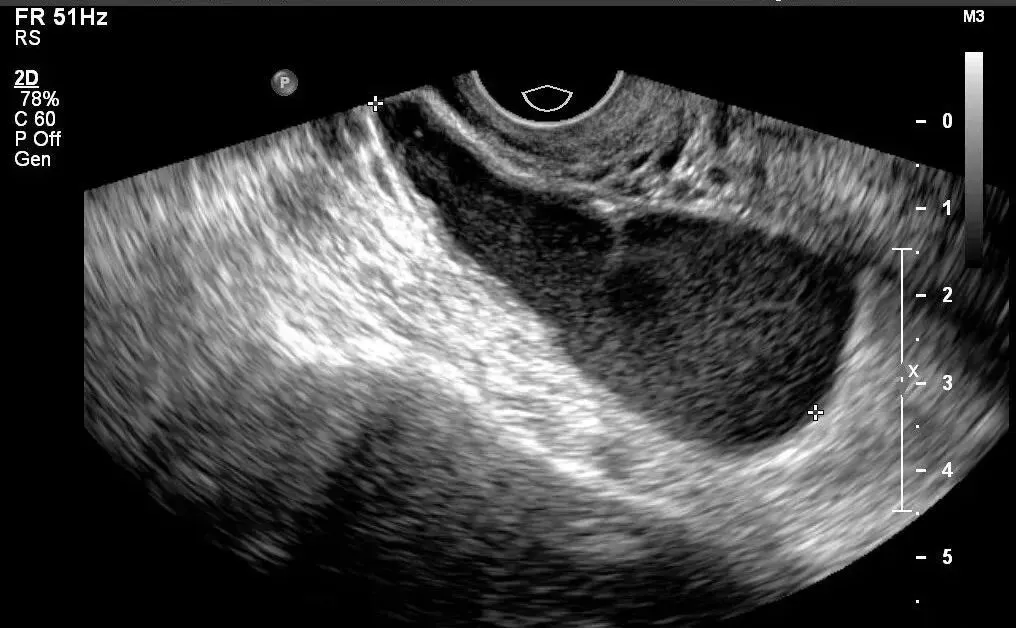

局灶性子宫内膜癌宫腔积血声像

子宫内膜癌侵犯浅肌层声像